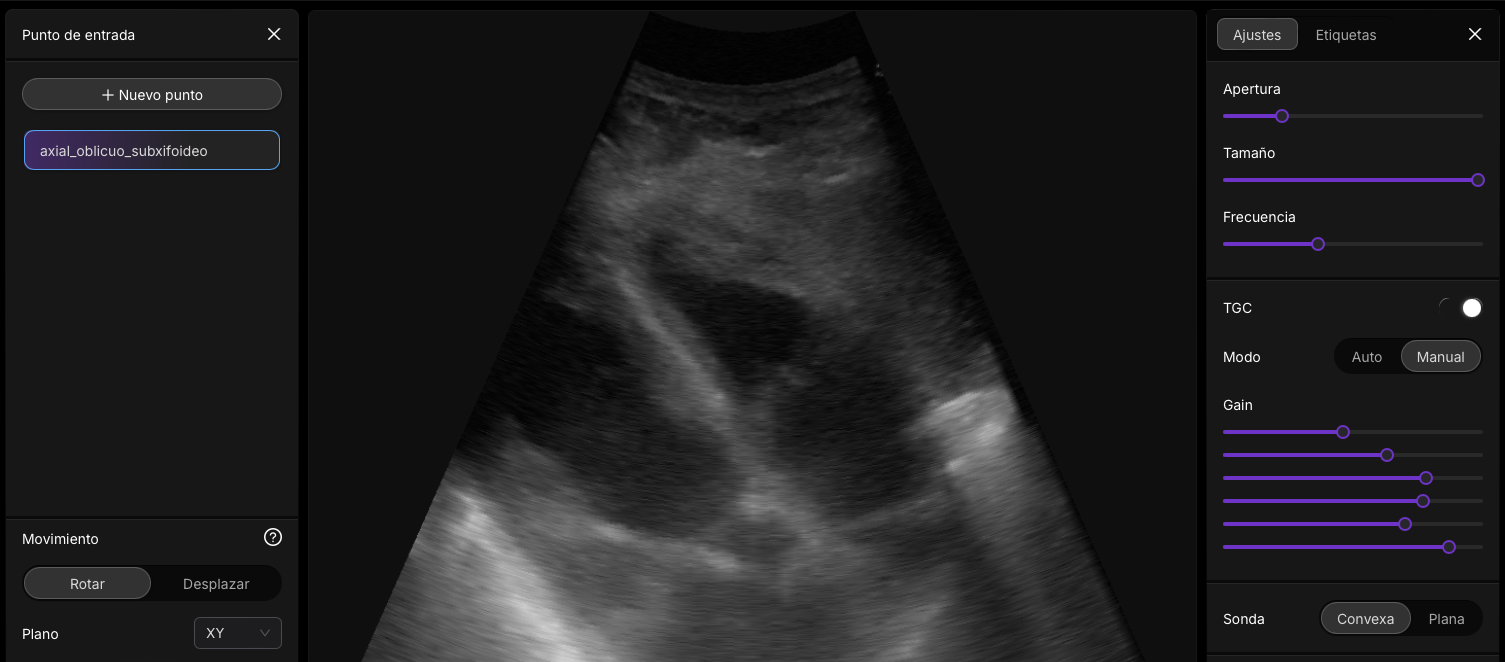

Esta intefaz de usuario, la podras encotnar en el modulo del curso II: Parametros nivel avanzado ( pronto)

Presets en Ecografía

Los presets ecográficos son configuraciones preestablecidas en los equipos de ultrasonido que están diseñadas para optimizar la calidad de la imagen según el tipo de estudio que se realizará. Cada preset ajusta parámetros clave como la frecuencia del transductor, la profundidad de escaneo, la ganancia (brillo general de la imagen), el enfoque y los filtros, de manera que las imágenes obtenidas sean adecuadas para el área anatómica en cuestión. Por ejemplo, al realizar un estudio abdominal, se seleccionará un preset que priorice una mayor profundidad de penetración y un menor nivel de detalle, ya que los órganos abdominales están situados más profundamente en el cuerpo. En contraste, un preset para estudios vasculares ajustará la configuración para captar flujos sanguíneos con mayor sensibilidad mediante modos Doppler y resoluciones más finas.

El uso de presets no solo facilita el trabajo del operador, sino que también garantiza una mayor uniformidad en los estudios realizados por distintos profesionales, permitiendo una comparación más precisa entre imágenes tomadas en diferentes momentos. Por ejemplo, un preset obstétrico está configurado para visualizar estructuras fetales, priorizando una alta resolución en planos superficiales y configuraciones de Doppler adaptadas a flujos fetales. En cambio, un preset musculoesquelético enfatizará imágenes detalladas de tejidos superficiales, como tendones y músculos, utilizando frecuencias más altas para lograr una resolución superior.

Ventanas Acústicas en Ecografía

Las ventanas acústicas son puntos o áreas del cuerpo desde donde las ondas sonoras del transductor pueden penetrar de manera óptima hacia las estructuras internas. Dado que el ultrasonido se transmite de manera más eficiente a través de tejidos homogéneos y con menor impedancia acústica, las ventanas acústicas permiten obtener imágenes más claras y detalladas de los órganos u otras estructuras anatómicas. Por ejemplo, en la evaluación del corazón mediante ecocardiografía transtorácica, la ventana acústica más común es entre las costillas, donde los ultrasonidos pueden evitar obstáculos como el aire de los pulmones y las costillas mismas.

El concepto de ventana acústica también se aplica en situaciones clínicas específicas. Por ejemplo, para evaluar el hígado, el operador puede aprovechar el epigastrio o el flanco derecho como ventanas acústicas, dado que el hígado se encuentra adyacente a la pared abdominal y ofrece un medio ideal para la transmisión del ultrasonido. En casos más complejos, como estudios craneales en neonatos, la fontanela sirve como una ventana acústica natural debido a la ausencia de hueso sólido, permitiendo visualizar estructuras intracraneales con facilidad. Las ventanas acústicas son, por tanto, fundamentales para maximizar la eficacia de los estudios ecográficos, adaptando la técnica según las características individuales del paciente.